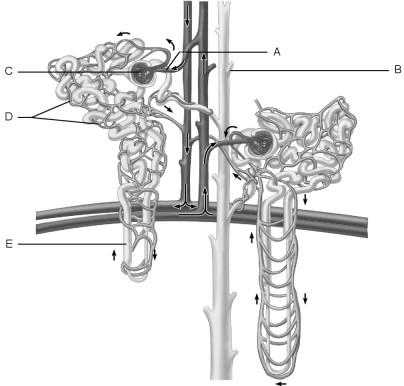

Afferent arteriole.

A

In the kidneys, the countercurrent mechanism involves the interaction between the flow of filtrate through the nephron loop of the juxtamedullary nephrons (the countercurrent multiplier) and the flow of blood through the limbs of adjacent blood vessels (the countercurrent exchanger). This relationship establishes and maintains an osmotic gradient extending from the cortex through the depths of the medulla that allows the kidneys to vary urine concentration dramatically.

TRUE or FALSE

TRUE

Cells that are most affected by ADH.

C

Cells that are the most active in reabsorbing the filtrate.

E

Medulla of the kidney.

E

Glomerulus.

C

Is composed of simple squamous epithelium.

A

Proximal convoluted tubule.

Site at which most of the tubular reabsorption occurs

Glomerulus.

Site of filtrate formation.

Peritubular capillaries.

Blood supply that directly receives substances from the tubular cells.

Collecting duct.

Site that drains distal convoluted tubule